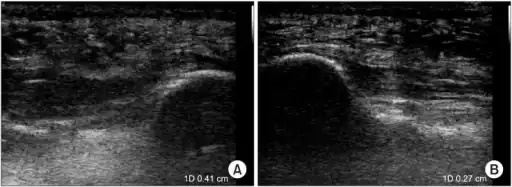

a)Ultrasonographic finding of plantar fasciitis b)normal sonographic finding -

The plantar fascia has three fascicles-the central fascicle being the thickest at 4 mm, the lateral fascicle at 2 mm, and the medial less than a millimeter thick.[18] In theory, plantar fasciitis becomes more likely as the plantar fascia's thickness at the calcaneal insertion increases. A thickness of more than 4.5 mm ultrasound and 4 mm on MRI are useful for diagnosis.[19] Other imaging findings, such as thickening of the plantar aponeurosis, are nonspecific and have limited usefulness in diagnosing plantar fasciitis.[13]